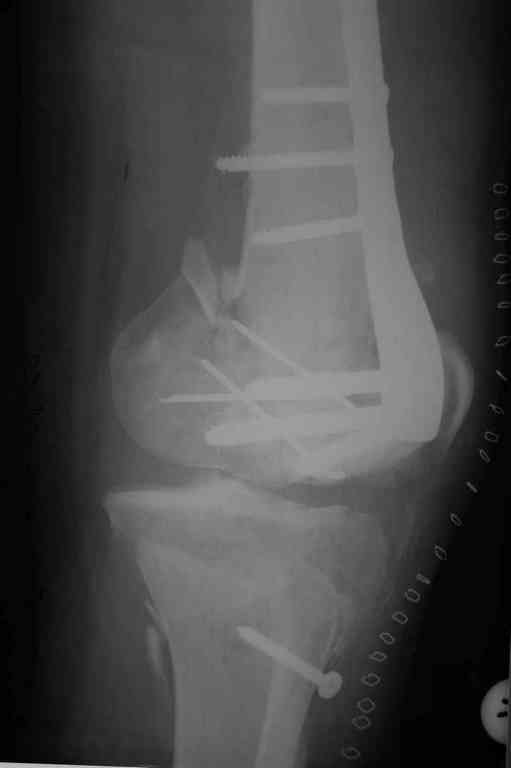

Re: Последствия открытого перелома дистального отдела бедра

Пожалуйста, снимки.